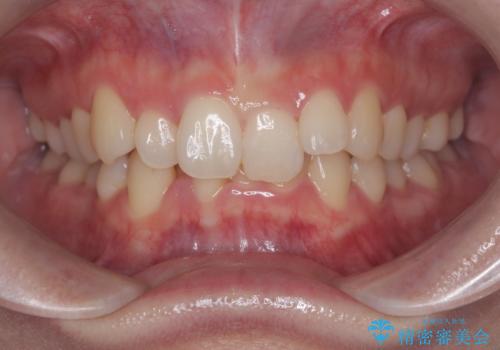

- 50代の患者様で、右上の八重歯と歯並びの乱れを気にされてご来院されました。特に、すでに装着されている前歯のセラミックブリッジを外したくないという強いご希望がありました。精密な検査の結果、八重歯を治すためのスペースが不足しているため、右上の4番目の歯(小臼歯)を抜歯し、そのスペースを利用して歯並び全体を整える治療計画を立案。装置には目立たないインビザラインを採用し、ブリッジを温存しながら八重歯の改善を目指しました。

今回の治療で最も重要だったのは、患者様のご要望通り既存のセラミックブリッジを外さずに矯正を進める点でした。計画通り右上の小臼歯を抜歯し、透明なインビザラインを使用して抜歯スペースを閉じながら、八重歯を正しい位置へ移動させました。ブリッジの形態と調和するに、他の歯の移動を工夫をすることで、複雑な条件をクリア。治療の結果、長年気にされていた八重歯が解消され、見た目が大きく改善しました。50代からでも、ご自身の要望を叶えながら、美しく機能的な歯並びを獲得していただけました。